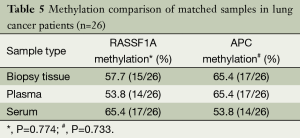

Sample type comparison

As listed in Table 5, the methylation rates of RASSF1A and APC of paired biopsy tissue, plasma and serum samples were all more than 50%. Data analysis revealed that the differences were not significant.

In the present study, we used multiple samples including plasma, serum and biopsy tumor tissues not only to improve methylation rate but also aimed to find out a much more suitable sample for DNA methylation detection. Firstly, our results of combined methylation rate of lung cancer patients had been highly improved to 88%. Secondly, methylation comparison of paired samples in lung cancer patients revealed that the methylation rates of the three different sample types were all around 60% and there was no significant difference among plasma, serum and biopsy tumor tissues. So we chose plasma as specimen with advantages of easy collection, minimal invasion and repetitive test.